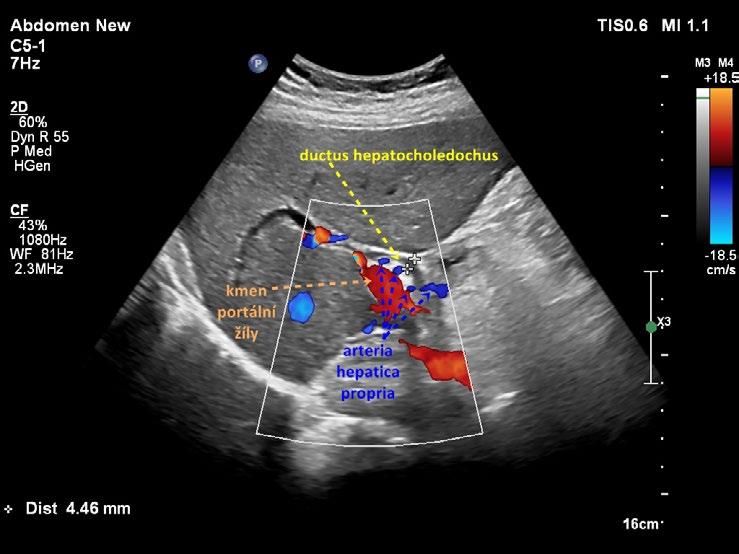

Žlučové cesty vyšetřujeme zpravidla v poloze na zádech. Je třeba systematicky prohlédnout celý objem jater alespoň ve dvou zobrazovacích rovinách tak, aby byl posouzen celý žlučový strom až do periferie. Žlučové cesty doprovázejí portální žilní systém od jaterního hilu až do periferie. Barevné dopplerovské mapování spolehlivě odliší žlučové cesty od portálního řečiště, popřípadě od jiných cévních struktur. K detailnímu zobrazení intrahepatických žlučovodů u primární sklerozující cholangoitidy (PSC) a jiných cholangiopatií využíváme lineární sondu. U chronických cholangiopatií současně sonograficky hodnotíme stav jaterního parenchymu a povrchu (jak konvexní, tak lineární sondou), průtokovou rychlost v portální žíle, přítomnost splenomegalie či portokaválních žilních spojek. U přístrojů, které disponují elastografickým vyšetřením, provádíme měření tuhosti jater.

Sonograficky nelze vizualizovat napojení ductus cysticus na společný žlučovod. Jinými slovy nelze posoudit, kde přechází ductus hepaticus communis do ductus choledochus. Z toho důvodu se v sonografické terminologii používá pro obě navazující části společného extrahepatického žlučovodu označení ductus hepatocholedochus (zkráceně